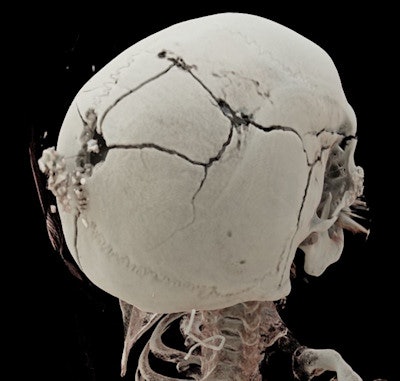

3D-rendered image shows the exit wound of a ballistic projectile in a neutral bloodless manner favored by juries and investigators. Image courtesy of Dr. Thomas Ruder.Ruder often uses a side-by-side comparison of antemortem images from local hospitals with postmortem CT images to identify subjects. Postmortem CT images may be reformatted to match almost any type of antemortem images, even high-quality ultrasound, he noted.